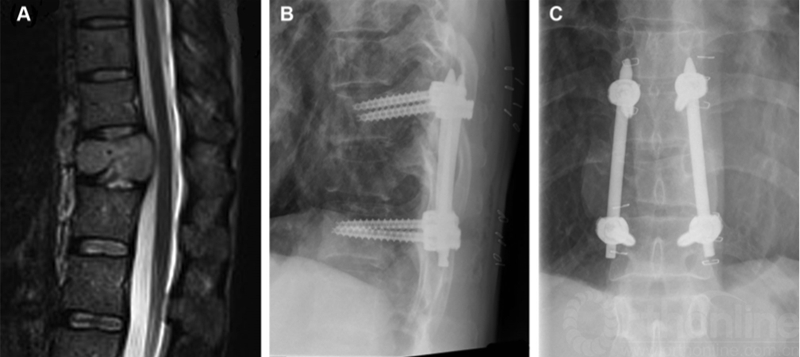

使用Jamshidi骨针和Kirschner导丝放置的经皮椎弓根螺钉已经彻底改变了后路固定的适应症(图1)。以前,对于预期寿命少于3个月的患者不建议进行手术。然而,临床医生往往难以正确估计患者的预期寿命38,而预期寿命较短的患者可能从减轻腰痛的内固定中受益。经皮椎弓根螺钉可用于预后不良的患者的姑息治疗和疼痛缓解,改变了内固定手术的适应证。经皮椎弓根螺钉常用于治疗腰椎退变性疾病,一些案例证明,与开放式方法相比,其并发症发生率较低,术后椎旁肌肉萎缩较少。39,40

图1经皮椎弓根螺钉系统。A,T11黑色素瘤转移患者的MRI表现,多发性皮损,肝,肺,脑转移,表现为背痛。B,侧位X线片显示经皮椎弓根螺钉姑息性治疗疼痛。C,正位X线片。